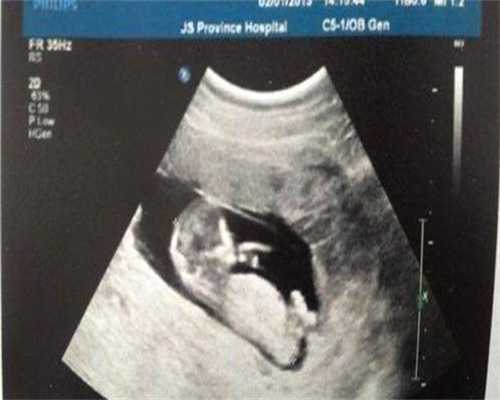

在进行人工授精前,医生通常会对女性卵巢进行监测,以确定卵泡的发育情况。如果卵巢中有过多成熟的卵泡,则可能会导致多个母细胞被受精并发育成胚胎,增加多胎的风险。因此在人工授精前进行卵泡监测是非常重要的,医生可以根据监测结果来调整受精方式,从而避免多胎的发生。